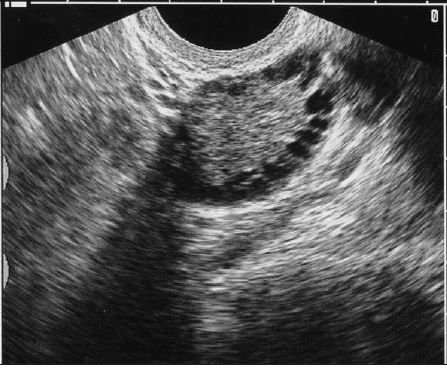

Ultrasonographic Characteristics. Despite recommendations of both the AE-PCOS and Rotterdam criteria that ovarian ultrasonographic characteristics be included in the diagnosis of PCOS, this guideline remains controversial.17,18 On an ultrasound, polycystic ovaries appear to contain multiple subcapsular follicles, a finding often referred to as “the string of pearls sign” (Figure 4). Formally, at least 1 of the following ultrasonographic characteristics should be present to categorize ovaries as polycystic in appearance:

• Twelve or more follicles that measure 2 to 9 mm in diameter.

• An increased ovarian volume of greater than 10 μL.

• A single ovary that meets either of the above criteria is sufficient for diagnosis.21

Figure 4.

A transvaginal ultrasonogram of an ovary of a patient with polycystic ovary

syndrome demonstrates multiple subcapsular follicles typical of polycystic-appearing ovaries.

The limited specificity of ultrasonography appears to be the main challenge to its widespread use in the diagnosis of PCOS in adults. Polycystic ovaries are found in up to 75% of women with oligoovulation, including many who do not have PCOS. Furthermore, up to 25% of healthy women have polycystic-appearing ovaries on an ultrasound.5 The shortcomings of ultrasonography in the diagnosis of PCOS are compounded in adolescents. Imaging the ovaries of adolescents via the transabdominal route-the preferred method in those who have not been sexually active-limits visualization and diagnostic accuracy.9,22 In addition, multifollicular ovaries have been identified in many healthy adolescents, and this finding may be confused with the polycystic pattern in PCOS.23Laboratory Evaluation. Expert agreement on a cutoff testosterone level that defines hyperandrogenemia has been challenging. Some argue that testosterone thresholds traditionally considered abnormal were improperly derived and that true biochemical hyperandrogenemia exists at lower testosterone levels than reported by many laboratories. Nevertheless, values ranging from 50 to 60 ng/dL or greater are considered abnormal compared with testosterone levels in women with normal menstrual cycles.5,24 In addition, a testosterone level of 200 ng/dL or greater (particularly in the setting of virilization) is an unequivocal indication to search for a testosterone-producing neoplasm.2,5